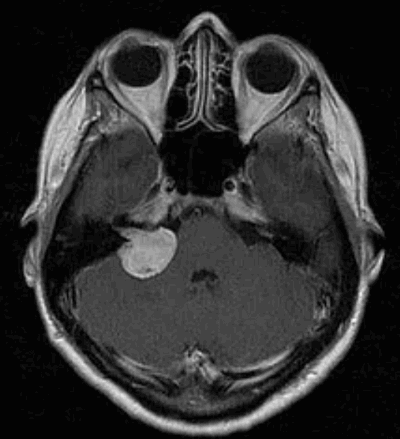

Наиболее информативным методом выявления вестибулярных шванном является МРТ головного мозга с контрастным усилением в режиме Т1 и Т2. Это исследование позволяет определить размеры опухоли, наличие перитуморозного отека, наличие признаков окклюзионной гидроцефалии, которая может быть следствием сдавления опухолью IV желудочка. Кроме этого МРТ позволяет провести дифференциальную диагностику с другими опухолями схожей локализации (чаще с менингиомой задней грани пирамиды височной кости). Еще одним стандартом диагностики является КТ в костном режиме. Независимо от снижения слуха стандартом является проведение аппаратной аудиографии.

Сканирование головы: если другие тесты показывают, что у пациента может быть вестибулярная шваннома, для подтверждения диагноза используется магнитно-резонансная томография (МРТ). МРТ использует магнитные поля и радиоволны, а не рентгеновские лучи для создания подробных изображений мозга. Томография показывает «срезы» мозга, которые можно объединить для создания трехмерного изображения опухоли. Часто пациенту вводят контрастный краситель. Опухоль впитывает больше красителя, чем нормальная ткань мозга, и будет четко видна на сканировании. МРТ обычно показывает опухоль во внутреннем слуховом проходе.

При асимметричной тугоухости МРТ с контрастированием гадолинием